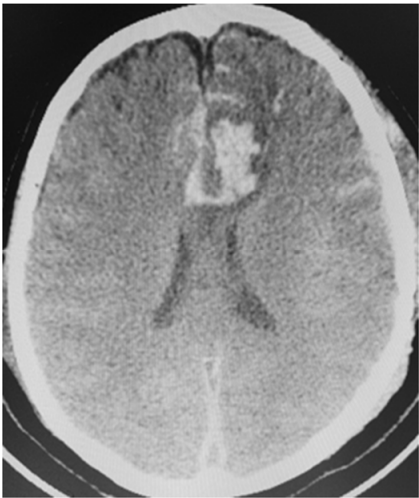

Uma paciente de 66 anos de idade, tabagista, hipertensa com tratamento irregular. Apresentou cefaleia súbita de severa intensidade associada a náuseas. Ao exame físico, observaramse AC = RR2T com BNF, FC = 100 bpm, AP = MVF sem RA, FR = 15 irpm, PA = 182 mmHg x 100 mmHg, SatO2 em ar ambiente = 97%, Glasgow 15, pupilas isofotorreagentes, sem deficits focais. TC crânio e arteriografia a seguir.

Fonte: Acervo pessoal.

Acerca desse caso clínico e com base nos conhecimentos médicos correlatos, julgue os itens a seguir.

Segundo a classificação da World Federation of Neurological Societies (WFNS), a paciente seria classificada como grau 1.